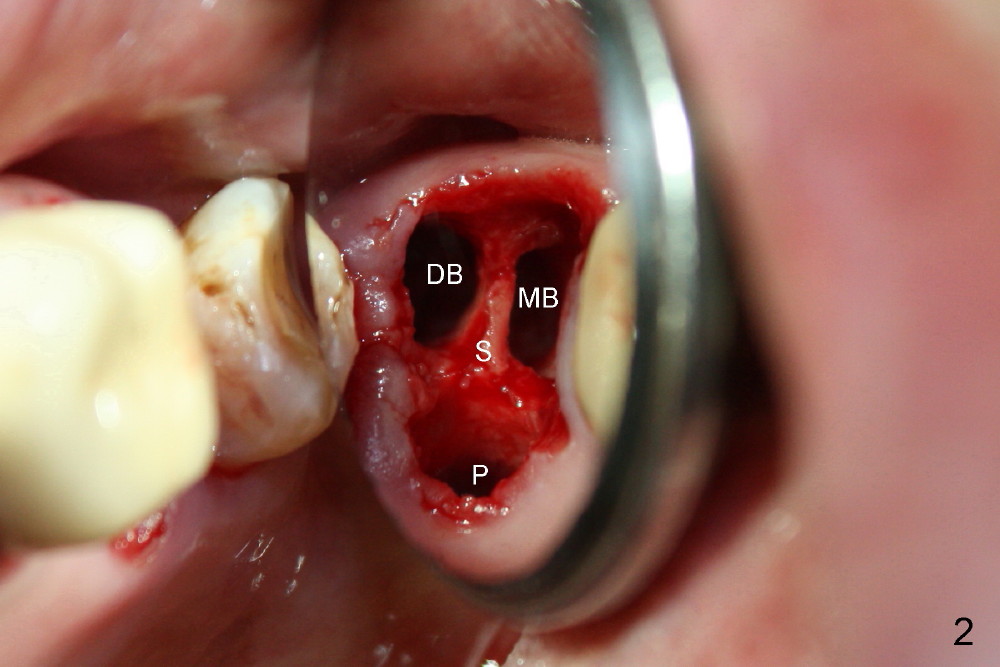

A 66-year-old lady requests restoring a broken tooth (Fig.1). Osteotomy is initiated in a thin septum (Fig.2 (occlusal mirror view) S) by sectioning, drilling and tapping (Fig.3 T). When 7x17 mm tap is removed, the osteotomy is found to form basically in the middle of socket (Fig.4 O). The apical portion of three sockets (Fig.5: MB, P and DB (not labeled) is packed with mixture of autogenous bone and allograft. When a 7x14 mm implant is placed, there are buccal and lingual gaps (Fig.6 *). The latter are bone grafted again (Fig.8 *) and require a coverage. After placement of a 4x3 mm abutment (Fig.7,8 A), an immediate provisional is fabricated (Fig.9 tissue surface view) to cover the remaining sockets (Fig.10 (occlusal mirror view), 11 (buccal view)). The provisional is infra-occlusal, i.e., load-free (Fig.11). The buccal and lingual aspects of the socket are covered by fresh epithelium 8 days postop (Fig.12 <). The implant appears to have osteointegrated 4 months postop (Fig.13). The tooth #16 appears to have shifted mesially. It is difficult to prepare for #15 crown. Luckily the patient agrees to have it extracted because of persistent sensitivity after MO composite. The definitive crown at the site of #15 is cemented 6 months postop (Fig.14).